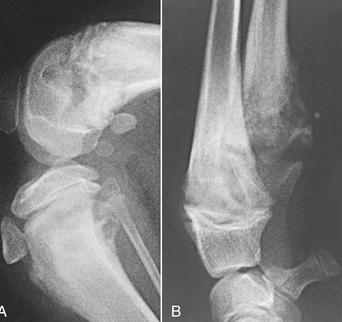

仪器检查后发现,白细胞总数增加,脓液培养可见腐生葡萄球菌生长。X光片发现其小腿部的骨组织呈现虫蚀样,通过扩创术深入了解后,确诊为骨髓炎,程度为急性状态。

实验室检查中,超声波可以提供更清晰的骨骼图像,骨骼中的脓液积聚。让兽医确定炎症的程度和需要治疗的部位。X光线可显示软组织肿胀,骨头周围纤维鞘的变化。